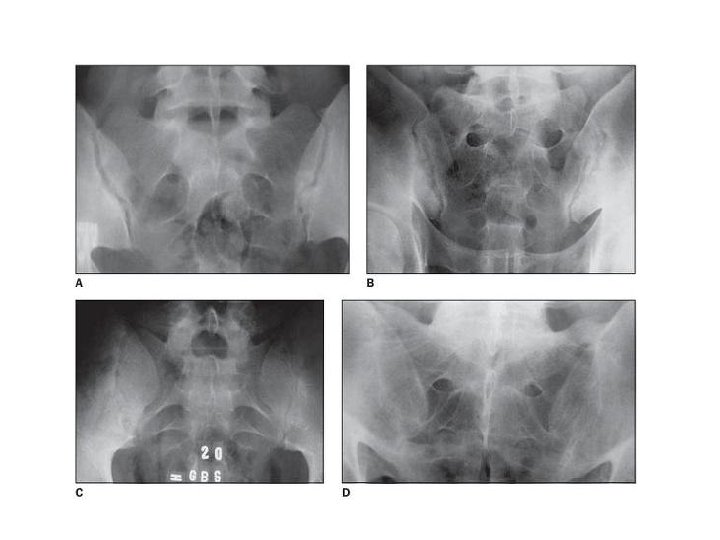

Summary • 1984년 modified NY criteria에 따르면 x-ray상 bilateral grade 2 이상 의 sacroiliitis가 필요 조건이다. • 2009년 ASAS 분류기준에 따라 axial spondyloarthritis (Ax. Sp. A)개념 이 생겼고 MRI 및 HLA-B 27 소견도 분류기준에 포함된다. • Ax. Sp. A 관련 증상으로 IBP, uveitis, IBD, Psoriasis, enthesitis, dactylitis, NSAID response, FHx, APR elevation 등이 있다. • 경추, 흉추, 요추의 spinal mobility 검사법이 다양하다. • 강직성 척추염의 척추증상 조절에 효과적인 약은 NSAIDs, TNF inhibitor이며, uveitis, IBD가 동반된 경우 anti-TNF monoclonal Abs 제제가 우선 고려될 수 있다.